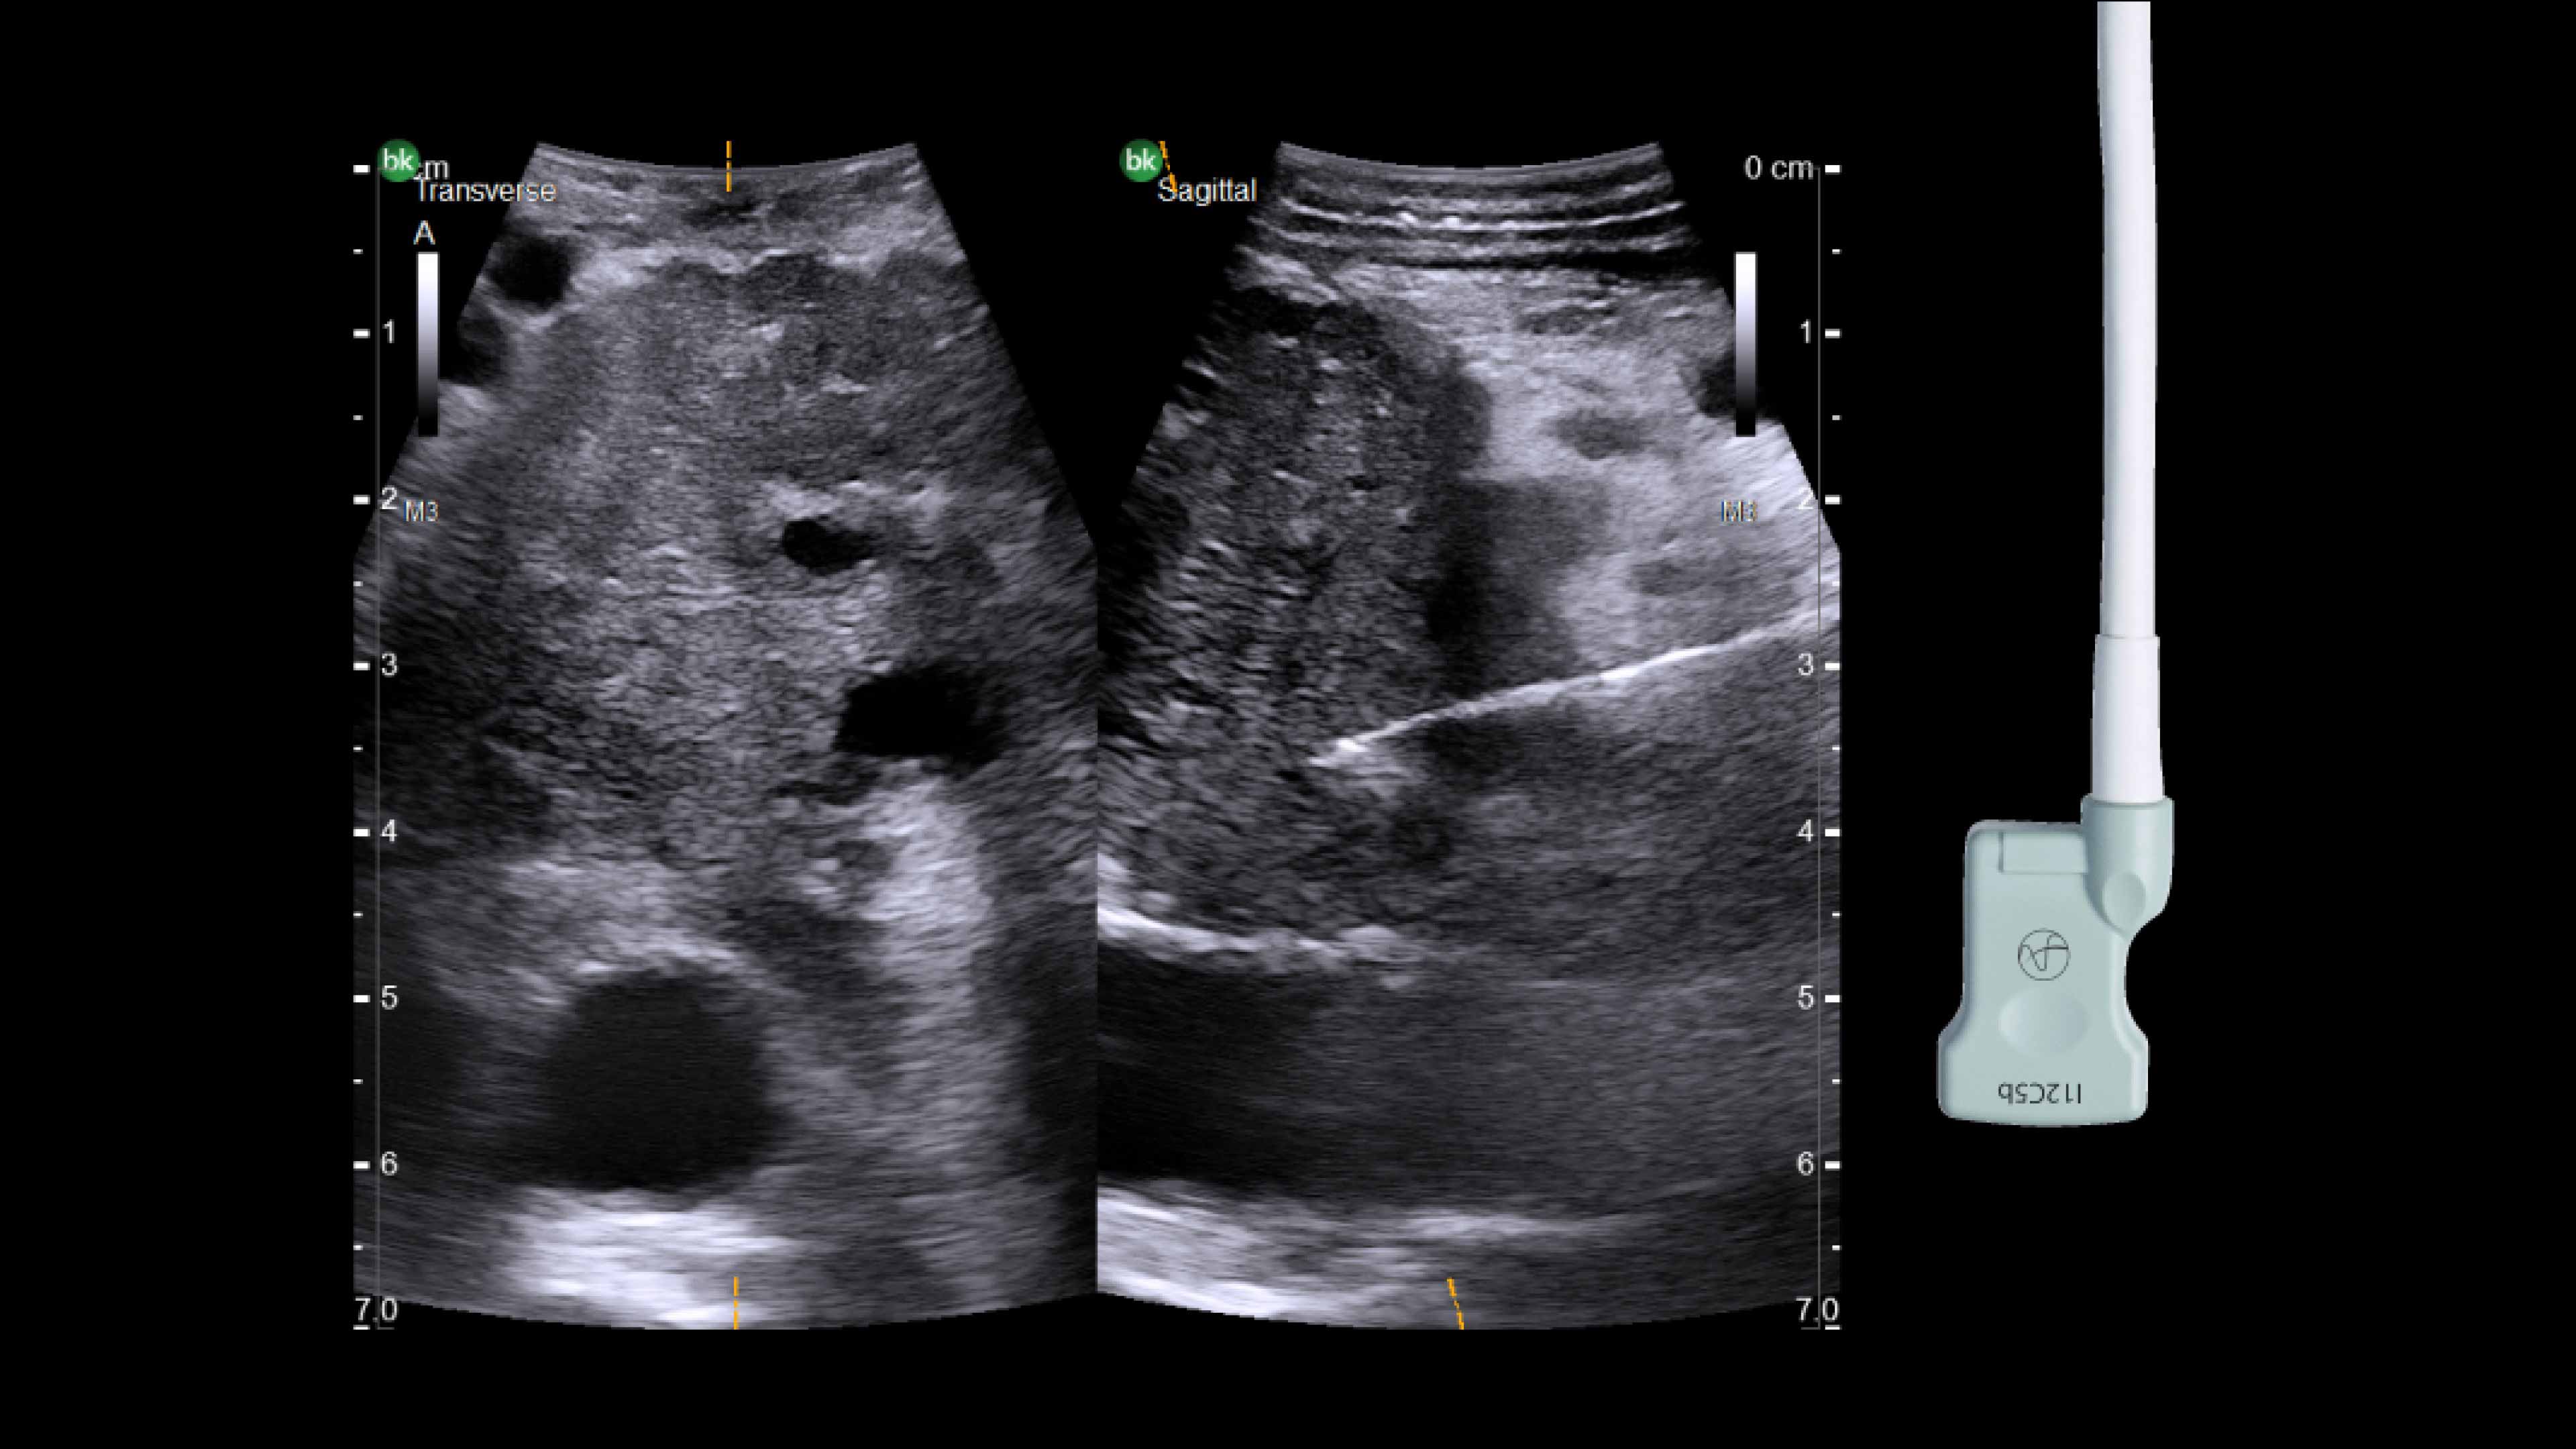

Active imaging supports liver and pancreas tumor resection procedures by helping you visualize complex anatomical variations and relationships to vascular structures, identify tumor location, define adequate margins of resection, and assess surgical planning.

Active imaging with intraoperative ultrasound supports critical decision-making in open or minimally invasive tumor resections.

• Visualize complex anatomical variations.

• Identify tumor location, proximity, and invasion of vasculature.

• Define adequate margins of resection.

• Understand relationship to vascular structures.

• Assess surgical planning and check for vessel patency at the end of the procedure.